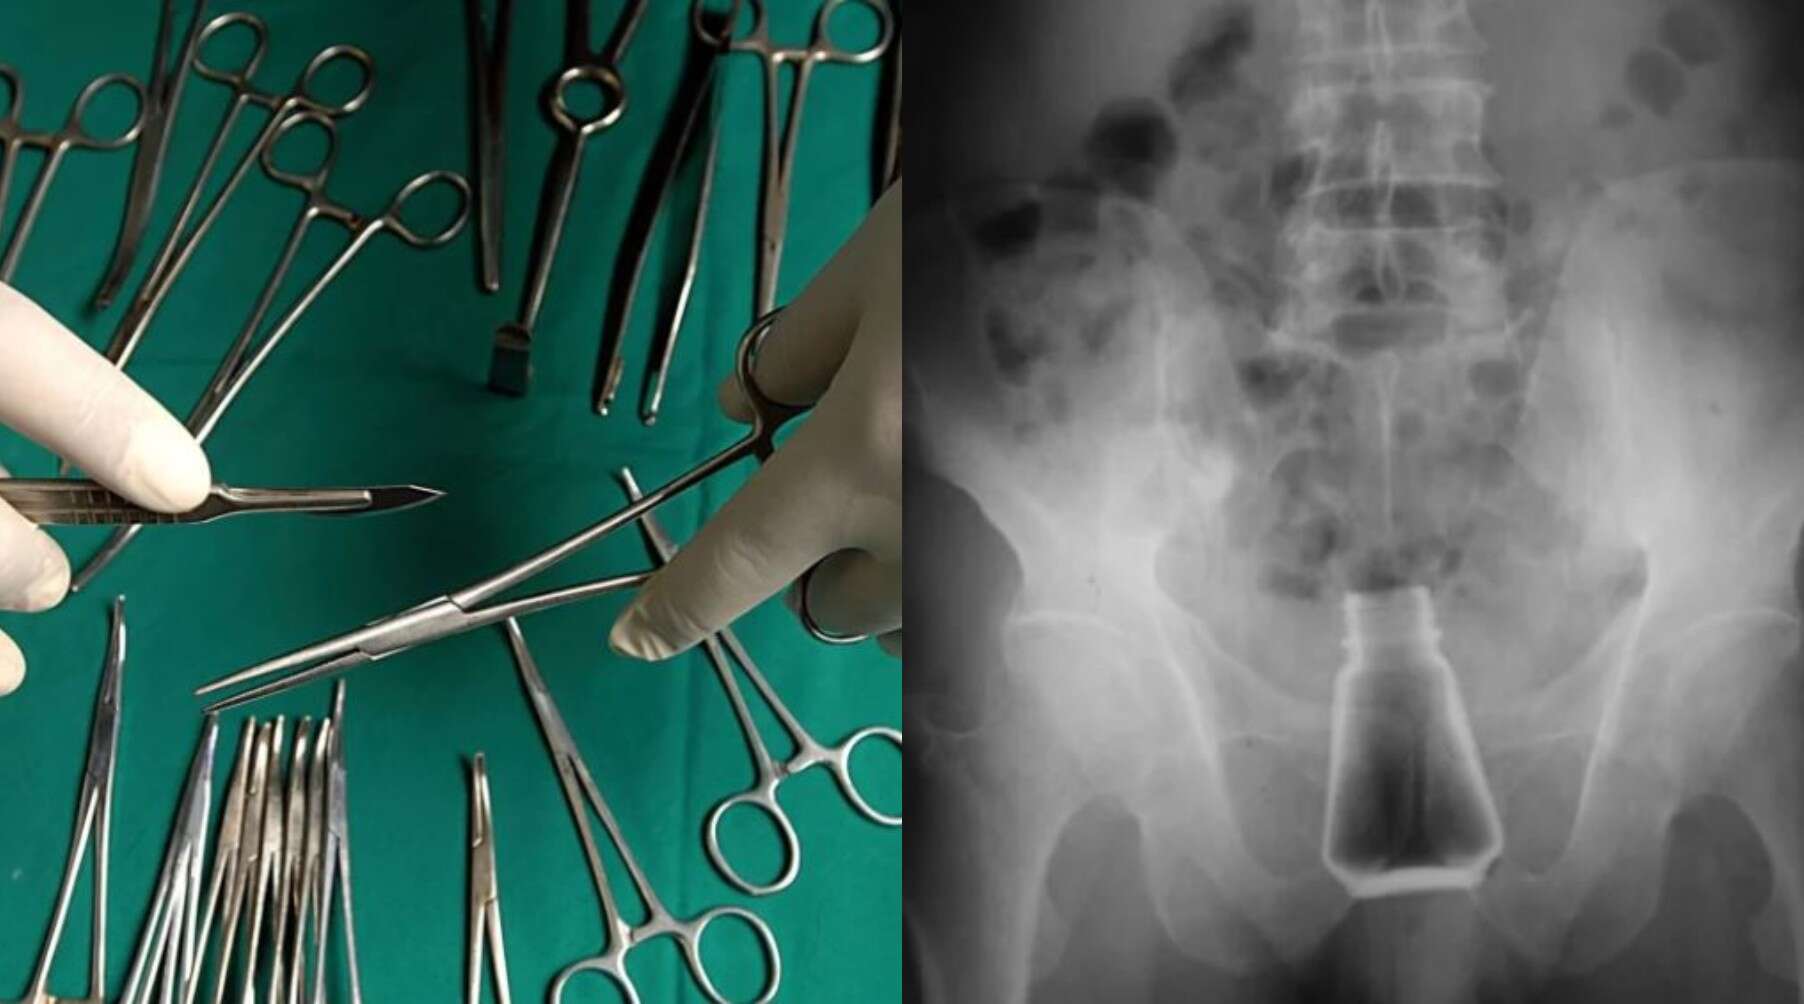

Ο ασθενής μεταφέρθηκε εσπευσμένα στο νοσοκομείο της Σύρου, καθώς κινδύνευε η ζωή του. Οι πληροφορίες του logotypos αναφέρουν ότι ο εν λόγω άνδρας είχε για δύο ολόκληρες ημέρες στον πρωκτό του το μπουκάλι με το αλάτι, καθώς ντρεπόταν να πάει σε γιατρό. Όπως αντιλαμβάνεστε, υπήρχαν φόβοι να πάθει σηψαιμία.

Αμέσως, ο ασθενής μπήκε στο χειρουργείο και του αφαιρέθηκε το αντικείμενο που υπήρχε στον πρωκτό του, προτού υπάρξουν πιο δυσάρεστες συνέπειες για την υγεία του.

Μάλιστα, σε ερώτηση του γιατρού του νοσοκομείου Σύρου, για το πώς βρέθηκε το μπουκάλι με το αλάτι στον πρωκτό του. Ο άνδρας υποστήριξε ότι ήταν ένα ατύχημα, καθώς έπεσε από σκάλα και προσγειώθηκε πάνω στο αλάτι.